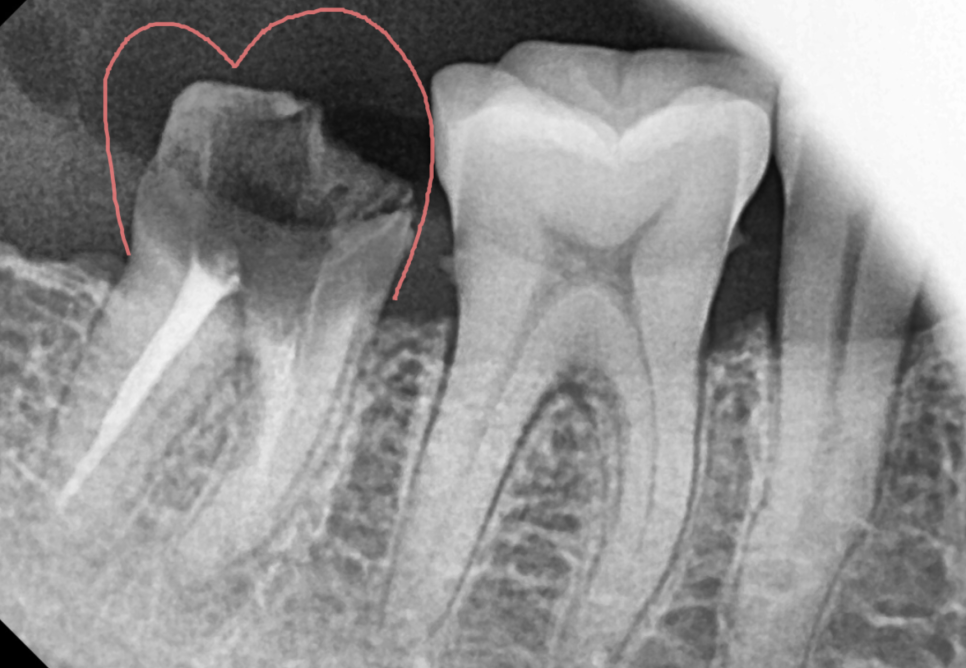

첫번째, 내부 충치

안쪽에 충치가 생길 경우

접착력이 약해져 빠질 수 있습니다.

보철 틈새 사이로 음식물과 세균이 들어가면서

발생하는 것이죠.

특히 신경치료 후 남은 내 치아가 별로 없거나

약했을 경우 더욱 쉽게 충치가 진행됩니다.

250327 내부 충치가 심한 경우